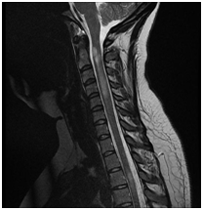

Anatómiai nyaki gerinc, láthatóvá MRI.

MRI lehetővé teszi, hogy megjelenítsék morfológiai változások: a csigolyatestek, porckorongok, gerincvelő, dura térben, az ideg gyökerek környező paravertebralis lágyrész, érrendszeri szerkezetek, amelyek a kutatási területen.

Jobb-paramedián, foraminalis porckorongsérv C6-C7.

Súlyos trauma a nyaki gerinc: a törés-zavar a C5 csigolya test, súlyos tömörítés az agytörzs, jeleivel gerincvelő-ödéma, a teljes gerinccsatorna szűkület szintjén a törés. MR kép prevertebrális vérömleny.

Ependimoma a gerincvelő. MR minta degeneratív változások a nyaki gerinc, a C5-C6 lemez extrudálás, C6-C7, C7-Th1.

Mr képet spondylosis, extrudált lemez C3-C4, C4-C5, C5-C6, C6-C7.